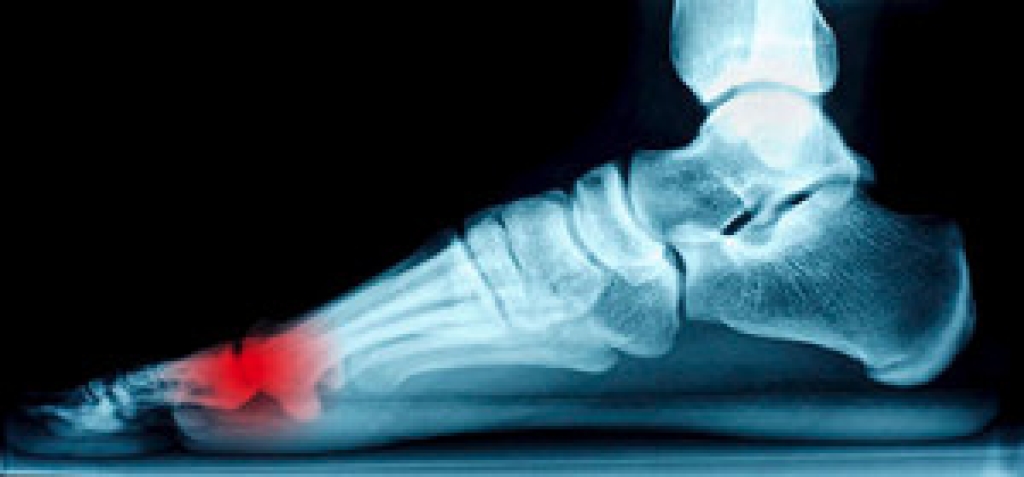

Sesamoiditis is a common condition among athletes in which inflammation occurs in the sesamoid bones in the feet. These bones, whose main function is to assist foot tendons in the movement of the big toe, can be injured either through athletic activity, such as dancing or running, or improper footwear like high heels. Symptoms include pain and inflammation, which can worsen with activities like walking. Diagnosis of sesamoiditis is conducted through bone scans or MRIs. The best way in which one can help manage sesamoiditis is by seeing a podiatrist, who may prescribe physical therapy, anti-inflammatory drugs, and rest to help the sesamoid bones to heal.

Sesamoiditis is a condition of the foot that affects the ball of the foot. It is more common in younger people than it is in older people. It can also occur with people who have begun a new exercise program, since their bodies are adjusting to the new physical regimen. Pain may also be caused by the inflammation of tendons surrounding the bones. It is important to seek treatment in its early stages because if you ignore the pain, this condition can lead to more serious problems such as severe irritation and bone fractures.

Treatment for sesamoiditis is non-invasive and simple. Doctors may recommend a strict rest period where the patient forgoes most physical activity. This will help give the patient time to heal their feet through limited activity. For serious cases, it is best to speak with your doctor to determine a treatment option that will help your specific needs.